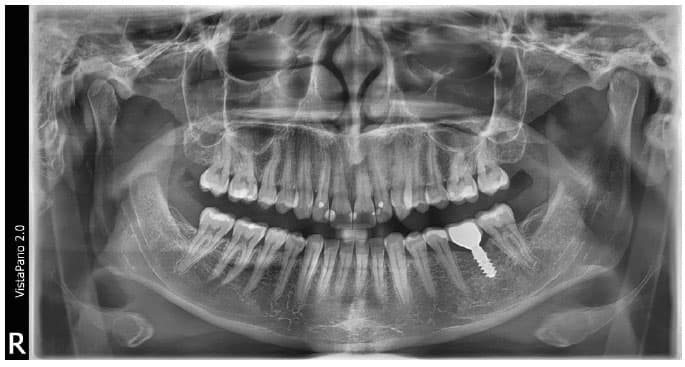

L’appareil numérique de radiographie panoramique doté de la technologie S-Pan

Avec le VistaPano S 2.0, Dürr Dental définit une nouvelle norme en termes de netteté d’image des clichés extra-oraux. Par ailleurs, l’appareil de radiographie panoramique 2D s’illustre par une utilisation simple et un flux de travail bien pensé, assisté par un écran tactile en verre 8" innovant. Le VistaPano S 2.0 offre un rendu exceptionnel, et ce grâce aux deux technologies innovantes qu’il intègre. D'une part, la technologie de capteur CsI innovante garantit une qualité d'image accrue permettant ainsi d'établir de meilleurs diagnostics. D'autre part, la technologie S-Pan exploite les données d'image du cliché individuel du patient pour montrer automatiquement une représentation panoramique parfaitement nette, et ce à chaque position spatiale de la mâchoire et des dents.

La technologie S-Pan : des images d'une netteté exceptionnelle pour des diagnostics sûrs

Contrairement à la méthode traditionnelle, la technologie S-Pan sélectionne automatiquement, parmi de nombreuses couches parallèles, les sections d’image qui représentent le mieux l’anatomie individuelle du patient. Lors de l’assemblage de l’image panoramique, les écarts par rapport à la « dentition moyenne » sont également pris en compte, tout comme l’inclinaison individuelle des dents. On obtient, par conséquent, une image d’une clarté exceptionnelle qui permet au dentiste de trouver immédiatement les structures pertinentes. Comme la reconstruction s'oriente en fonction de la situation effective de la dentition, les erreurs de positionnement sont « compensées » dans certaines limites. Ainsi, le cabinet gagne du temps, et le client ne subit aucune répétition de clichés.